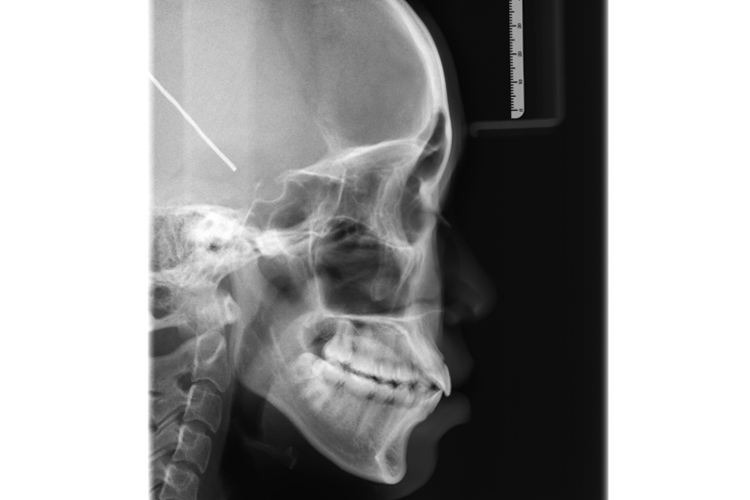

牙齿咬合指牙齿接触,牙齿咬合关系指咀嚼时牙齿接触关系,牙齿咬合关系分为正中咬合和非正中咬合,X光即X线片表现有所差异。

牙齿咬合关系分为正中咬合和非正中咬合,非正中咬合又分为前伸咬合及侧咬合,X线片表现有所差异。

下颌在正中位时,上下颌牙尖窝交错、最广泛地均匀接触。